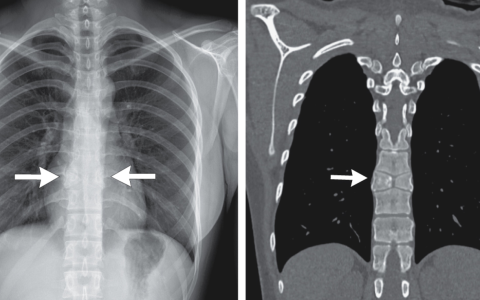

该患者的长期糖尿病最有可能引起神经源性膀胱。膀胱过度充盈可能导致膀胱输尿管反流至肾脏。当细菌性尿路感染叠加在反流物上时,会导致肾损伤。慢性肾盂肾炎导致肾脏肾盏变钝和增厚,瘢痕不均匀。如果由于某些先天性解剖异常,这种情况可能发生在单侧。上图显示,慢性肾盂肾炎肾盏内有鹿角形结石充盈,皮质和髓质萎缩,肾盏扩张。鹿角形结石(鸟粪石结石)与慢性感染有关,通常与产脲酶微生物有关,如变形杆菌。鸟粪石的典型诊断线索是碱性尿。